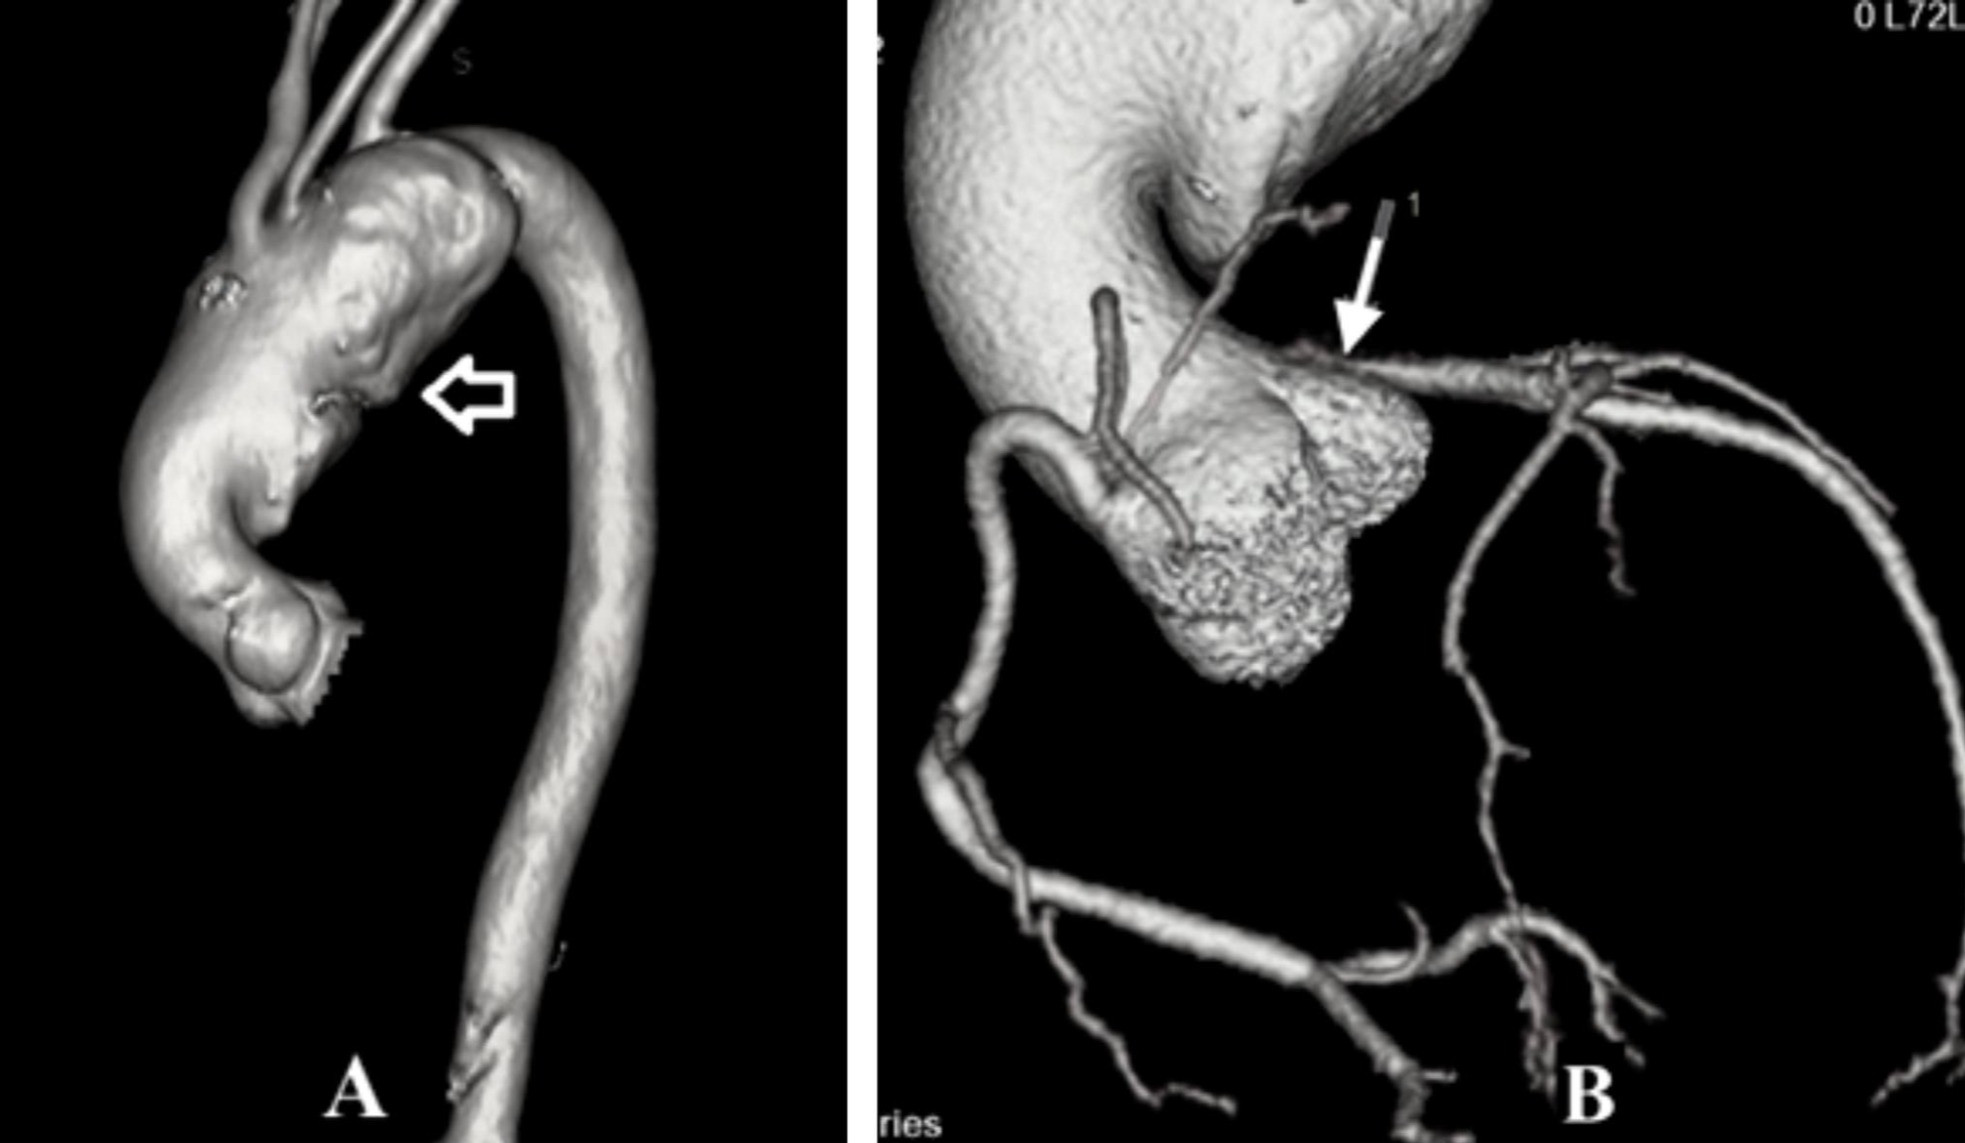

Bệnh nhân nam, 50 tuổi, quê Nghệ An, đi khám Bệnh viện Đại học Y Hà Nội vì tức ngực trái, khó thở khi gắng sức. Ông được chẩn đoán phình động mạch chủ khổng lồ, nếu không phát hiện kịp thời có thể bị vỡ, tử vong bất cứ lúc nào.

Theo Tiến sĩ Vũ Ngọc Tú, Trung tâm Tim mạch, Bệnh viện Đại học Y Hà Nội, khối phình động mạch chủ khổng lồ là căn nguyên chính chèn ép gây tắc động mạch vành trái, hở van hai lá nhiều, giãn lớn và giảm nặng chức năng co bóp của cơ tim, dẫn đến triệu chứng khó thở, khiến người bệnh phải đi khám.

“Đây là trường hợp hy hữu vì hầu như không thể có khối phình động mạch chủ tới 10cm mà chưa vỡ, chưa kể việc bệnh nhân có thể sống với quả tim giãn lớn, van tim hở nặng và chỉ một động mạch vành phải nuôi tim”, bác sĩ Tú cho biết.

Sau 3 ngày phẫu thuật, người bệnh được rút nội khí quản, tỉnh táo, chức năng các tạng được duy trì ổn định. Các kết quả chẩn đoán hình ảnh của người bệnh trước khi ra viện cho thấy khối phình động mạch chủ được xử lý triệt để, động mạch vành bị tắc được tái tạo, van hai lá sau tạo hình và kích thước buồng tim trở lại giống như ở người bình thường.